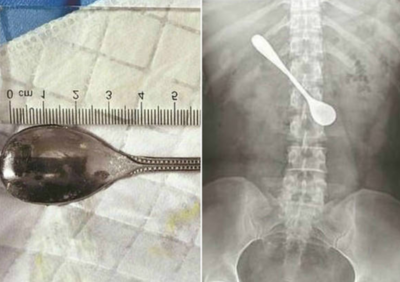

Um mulher passou quatro dias com uma colher alojada no intestino, segundo o R7. Ela tentava retirar una espinha quando engoliu o objeto mecânico de 13 cm. Ela não procurou auxílio médico imediato por achar difícil ser atendida durante um festival local.